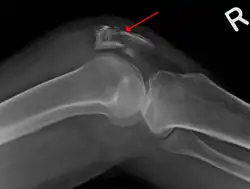

| A fracture of the patella seen on a lateral view | |

Osteochondral fracture of patella -